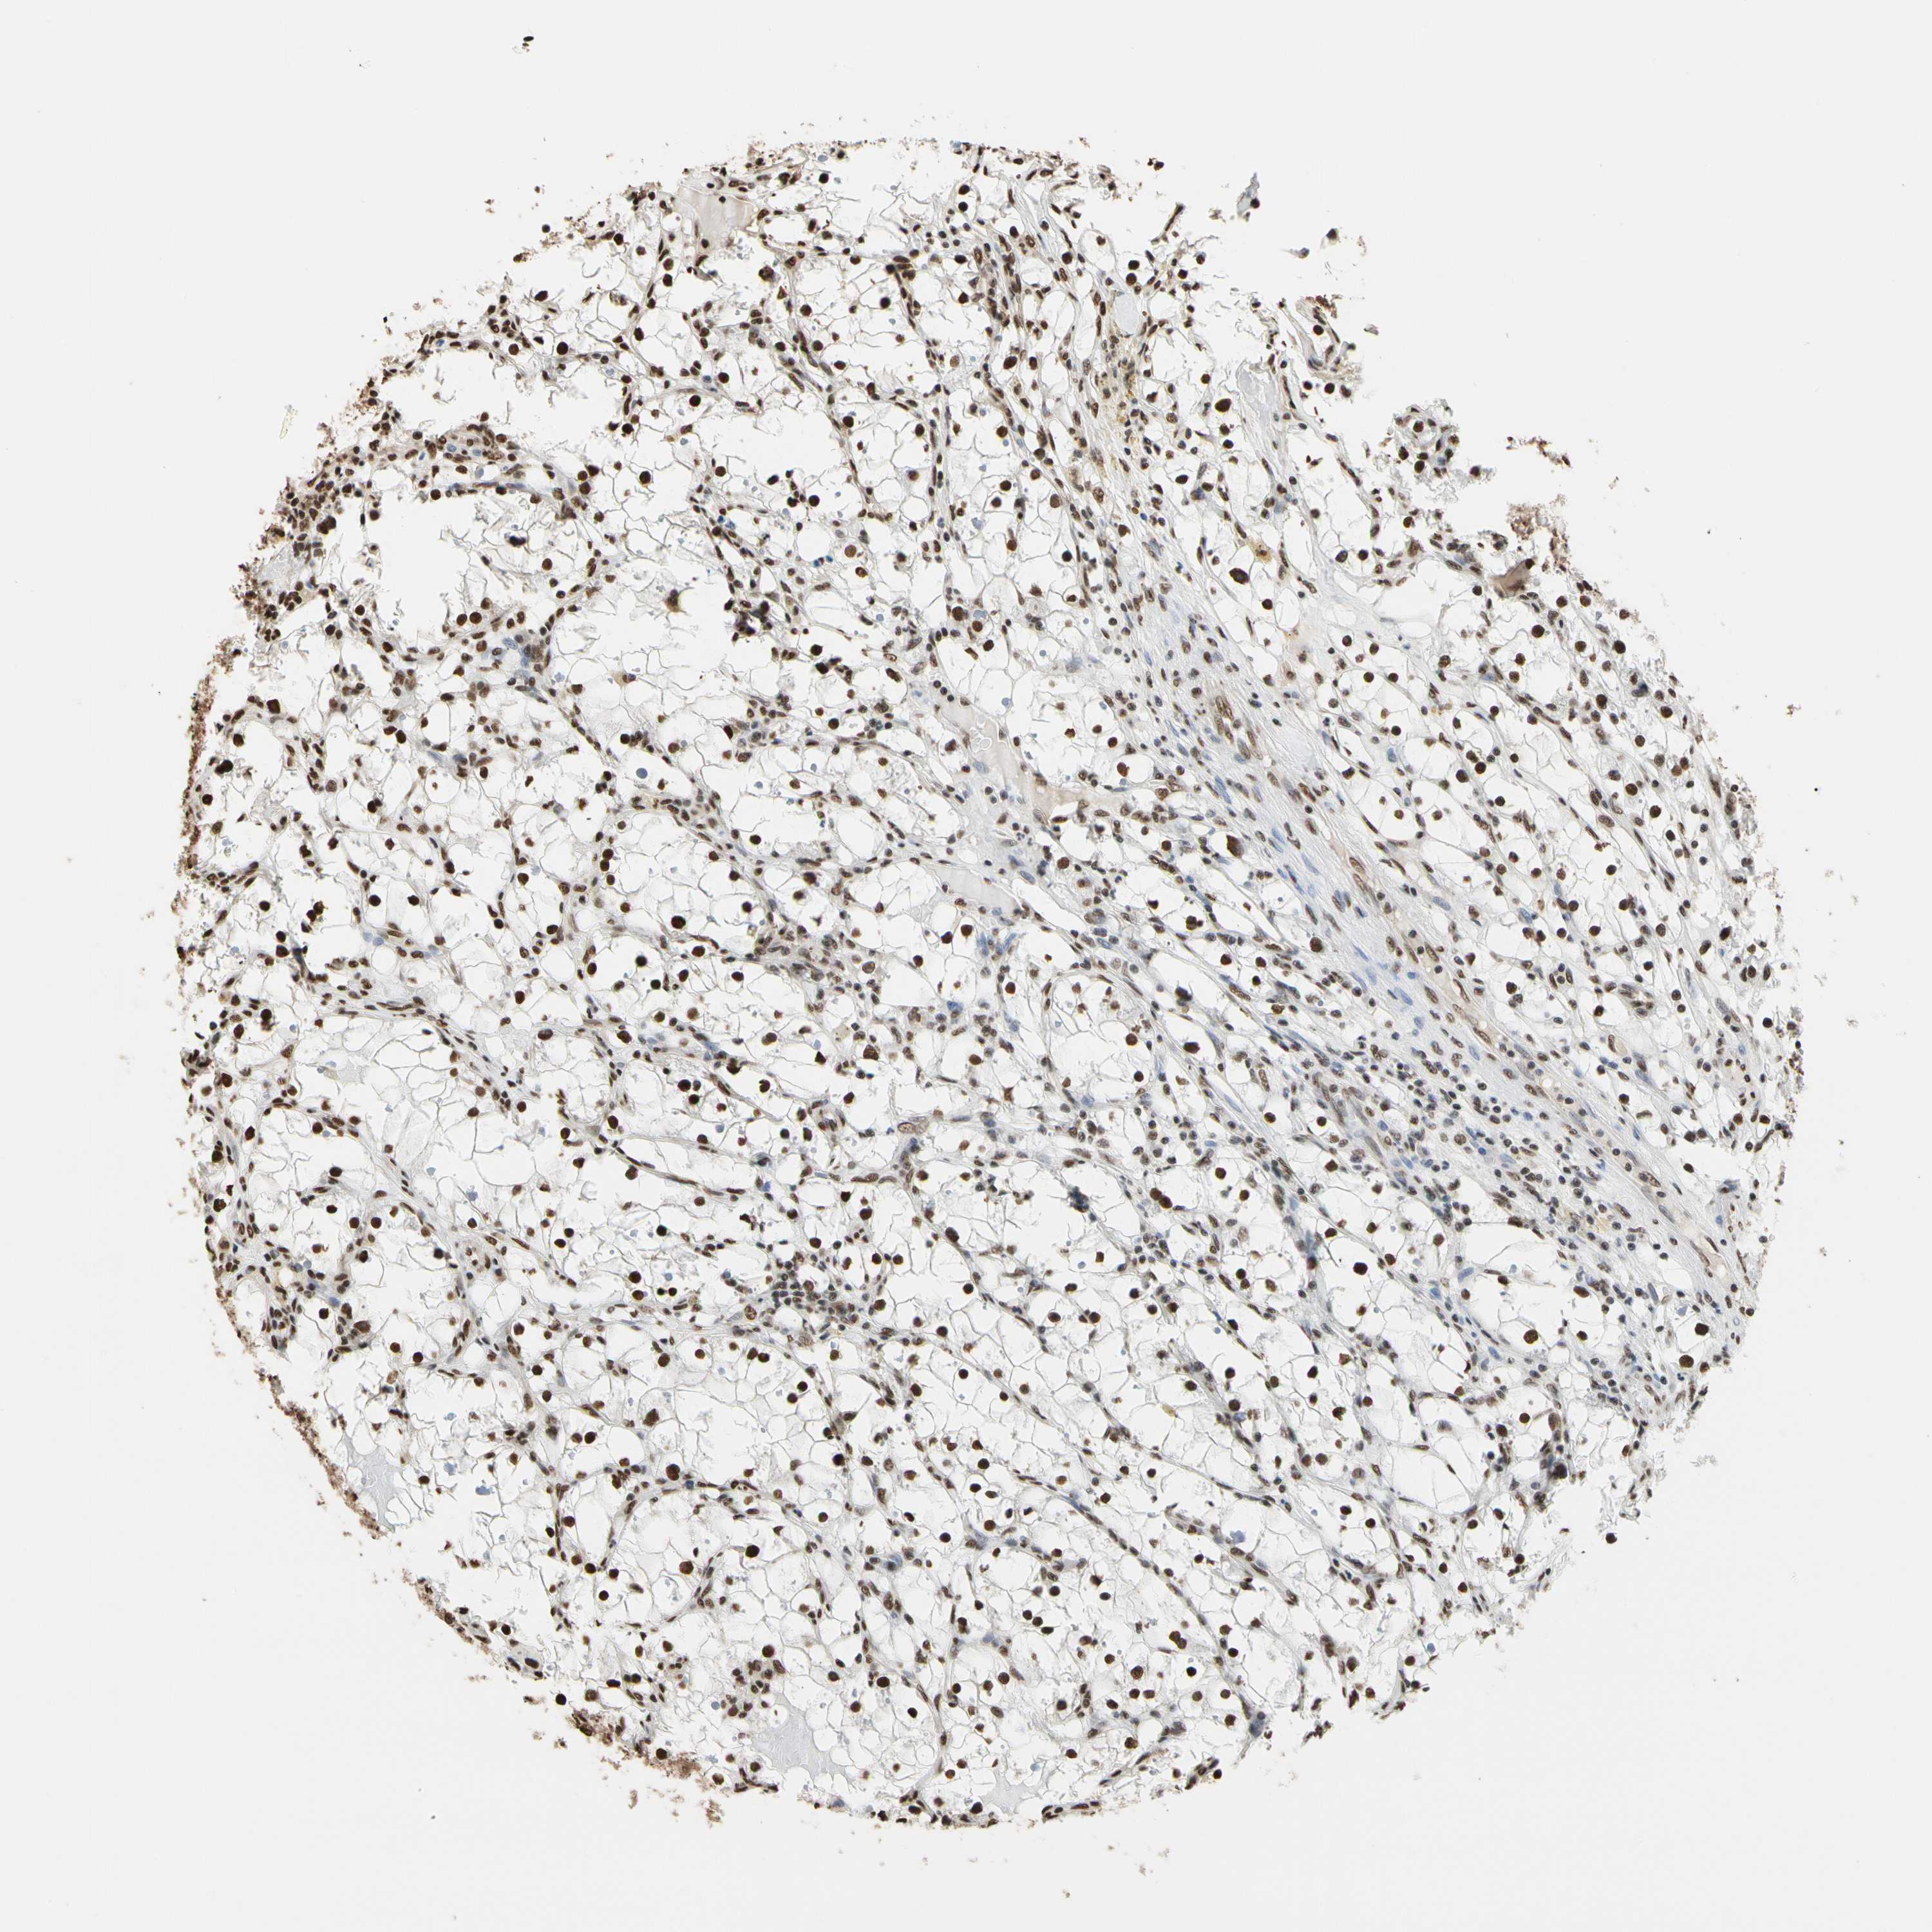

HNRNPK is not prognostic in Kidney Chromophobe (TCGA)

Best expression cut offi

Based on the FPKM value of each gene, patients were classified into two groups and association between prognosis (survival) and gene expression (FPKM) was examined. The best expression cut-off refers the FPKM value that yields maximal difference with regard to survival between the two groups at the lowest log-rank P-value. Best expression cut-off was selected based on survival analysis .

When clicking on this number, the vertical dashed line indicating cut-off, the interactive survival plot, and the Kaplan-Meier curve will be adjusted to show results based on the best expression cut-off.

: 241.96

P scorei

Log-rank P value for Kaplan-Meier plot showing results from analysis of correlation between mRNA expression level and patient survival.

N/A

5-year survival highi

5-year survival for patients with higher expression than the expression cutoff.

For melanoma and glioma, 3-year survival is shown.

5-year survival lowi

5-year survival for patients with lower expression than the expression cutoff.

Average pTPM 291.9

Number of samples 64